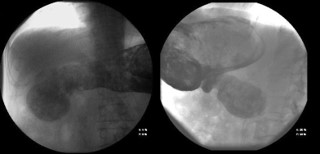

The patient followed an excellent clinical course, with full resolution of the symptoms after three months of treatment. The follow-up CT scan obtained three months (Figure 3) and six months (Figure 4) after admission revealed the complete dissolution of the bezoar. Annual clinical follow-up was performed until June 2025, with no recurrence of symptoms of bezoar reformation.

Figure 3: Computed tomography scan at three-month follow-up.